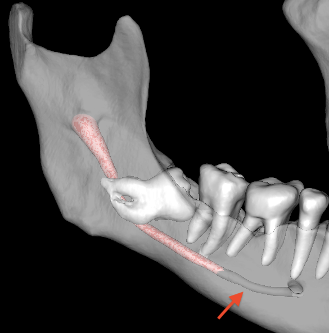

Another limitation is that Diagnocat segmentation results in a wide segmentation of the IAC at the mandibular entrance. In contrast, the semi-automatic method yields a narrow segmentation at the same location. This discrepancy in segmentation width may lead to errors when the results of the 2 methods are overlapped and compared (Figure 6).

Additionally, in the case of the AI-based automatic segmentation, the algorithm did not correctly detect the IAC in some areas of the CBCT image. This resulted in an underestimation or even complete absence of the IAC diameter, which in turn led to the exclusion of portions of the 3D model (Figure 7).